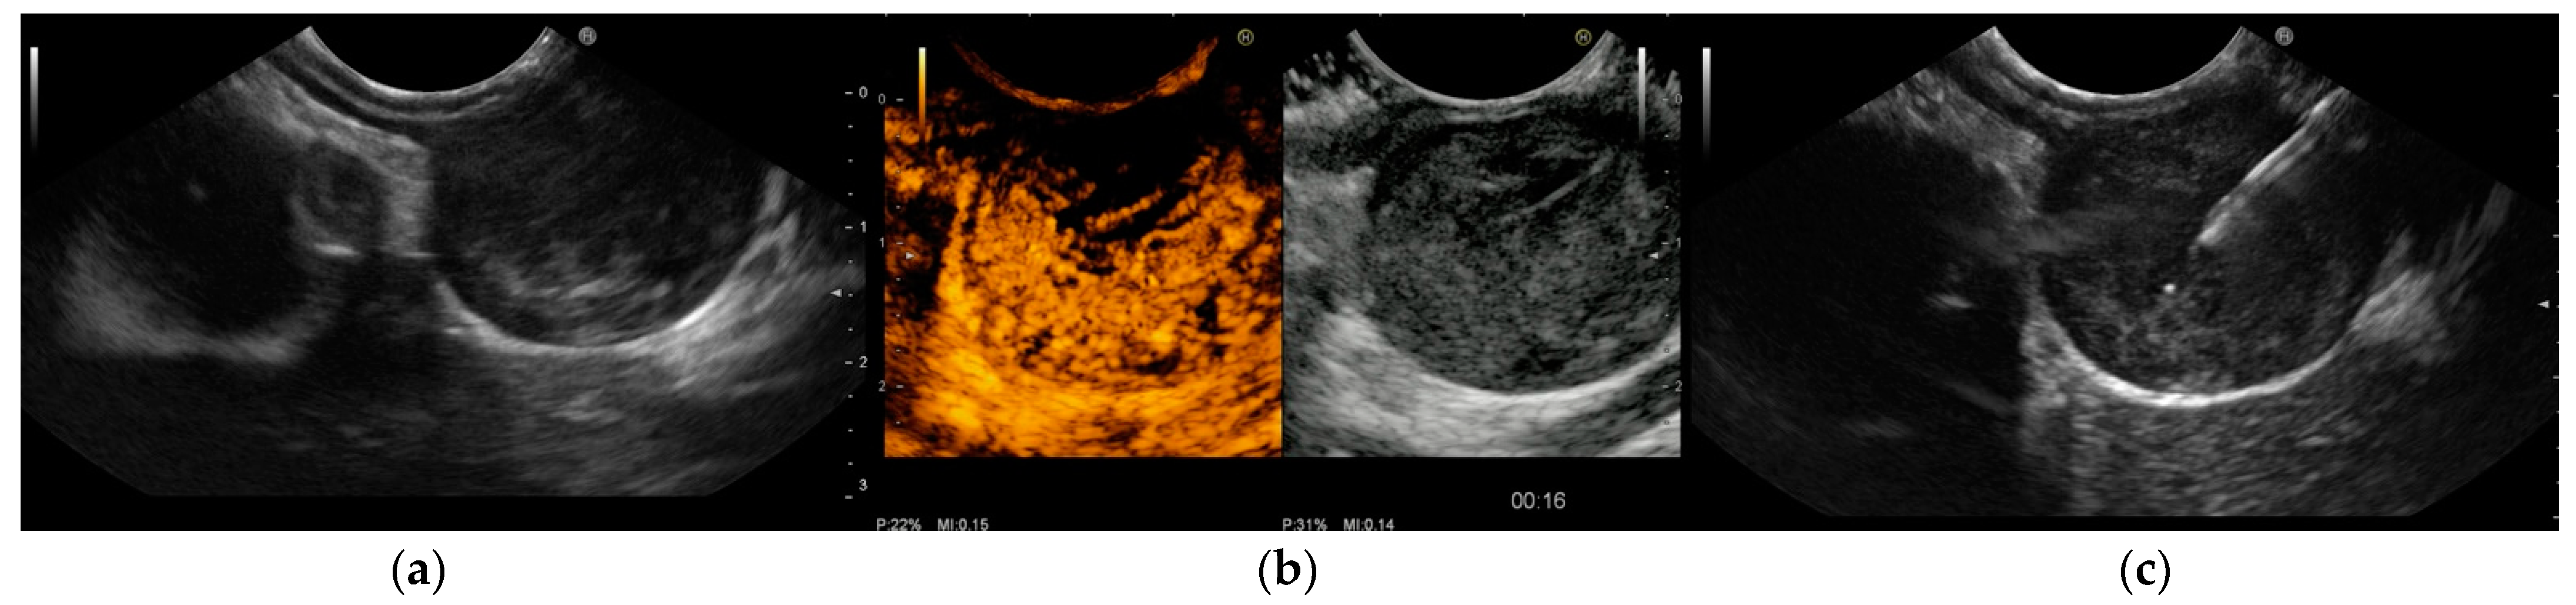

- Sakamoto, H.; Kitano, M.; Matsui, S.; Kamata, K.; Komaki, T.; Imai, H.; Dote, K.; Kudo, M. Estimation of malignant potential of GI stromal tumors by contrast-enhanced harmonic EUS (with videos). Gastrointest. Endosc. 2011, 73, 227–237. [Google Scholar] [CrossRef]

- Ignee, A.; Jenssen, C.; Hocke, M.; Dong, Y.; Wang, W.P.; Cui, X.W.; Woenckhaus, M.; Iordache, S.; Saftoiu, A.; Schuessler, G.; et al. Contrast-enhanced (endoscopic) ultrasound and endoscopic ultrasound elastography in gastrointestinal stromal tumors. Endosc. Ultrasound. 2017, 6, 55–60. [Google Scholar] [CrossRef]

- Kannengiesser, K.; Mahlke, R.; Petersen, F.; Peters, A.; Ross, M.; Kucharzik, T.; Maaser, C. Contrast-enhanced harmonic endoscopic ultrasound is able to discriminate benign submucosal lesions from gastrointestinal stromal tumors. Scand. J. Gastroenterol. 2012, 47, 1515–1520. [Google Scholar] [CrossRef] [PubMed]

- Yamashita, Y.; Kato, J.; Ueda, K.; Nakamura, Y.; Abe, H.; Tamura, T.; Itonaga, M.; Yoshida, T.; Maeda, H.; Moribata, K.; et al. Contrast-enhanced endoscopic ultrasonography can predict a higher malignant potential of gastrointestinal stromal tumors by visualizing large newly formed vessels. J. Clin. Ultrasound 2015, 43, 89–97. [Google Scholar] [CrossRef] [PubMed]

- Kamata, K.; Takenaka, M.; Kitano, M.; Omoto, S.; Miyata, T.; Minaga, K.; Yamao, K.; Imai, H.; Sakurai, T.; Watanabe, T.; et al. Contrast-enhanced harmonic endoscopic ultrasonography for differential diagnosis of submucosal tumors of the upper gastrointestinal tract. J. Gastroenterol. Hepatol. 2017, 32, 1686–1692. [Google Scholar] [CrossRef] [PubMed]

- Park, H.Y.; Jeon, S.W.; Lee, H.S.; Cho, C.M.; Bae, H.I.; Seo, A.N.; Kweon, O.K. Can contrast-enhanced harmonic endosonography predict malignancy risk in gastrointestinal subepithelial tumors? Endosc. Ultrasound 2016, 5, 384–389. [Google Scholar] [PubMed]

- Cho, I.R.; Park, J.C.; Roh, Y.H.; Choi, S.I.; Lee, J.E.; Kim, E.H.; Shin, S.K.; Lee, S.K.; Lee, Y.C. Noninvasive prediction model for diagnosing gastrointestinal stromal tumors using contrast-enhanced harmonic endoscopic ultrasound. Dig. Liver Dis. 2019, 51, 985–992. [Google Scholar] [CrossRef] [PubMed]

- Lee, H.S.; Cho, C.M.; Kwon, Y.H.; Nam, S.Y. Predicting Malignancy Risk in Gastrointestinal Subepithelial Tumors with Contrast-Enhanced Harmonic Endoscopic Ultrasonography Using Perfusion Analysis Software. Gut Liver 2019, 13, 161–168. [Google Scholar] [CrossRef] [PubMed]

- Lefort, C.; Gupta, V.; Lisotti, A.; Palazzo, L.; Fusaroli, P.; Pujol, B.; Gincul, R.; Fumex, F.; Palazzo, M.; Napoléon, B. Diagnosis of gastric submucosal tumors and estimation of malignant risk of GIST by endoscopic ultrasound. Comparison between B mode and contrast-harmonic mode. Dig. Liver Dis. 2021, 53, 1486–1491. [Google Scholar] [CrossRef]